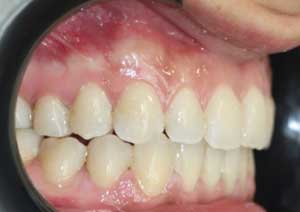

En orthodontie, une béance antérieure est une malocclusion caractérisée par l’absence de contact entre les incisives supérieures et inférieures lorsqu’on ferme les dents.

Traitement : Une ingression des molaires maxillaires avec une égression contrôlée du secteur antérieur a été réalisée à l’aide des arcs dits “Rocking Chair”, associés à des élastiques antérieurs portés de canine à canine, à droite et à gauche.

Cette mécanique permet de corriger la béance antérieure tout en conservant un contrôle précis de la position des dents antérieures et postérieures.

Avant